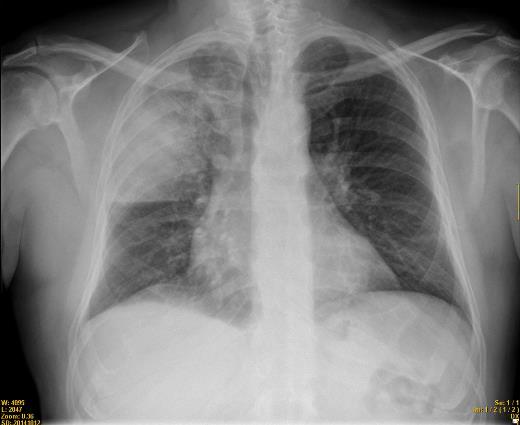

Los pacientes presentaron neumonía bilateral y fueron conectados a un respirador. El sanatorio donde se registró este brote ha sido aislado, no se reciben más pacientes y se han reforzado las medidas de seguridad contra los contagios.